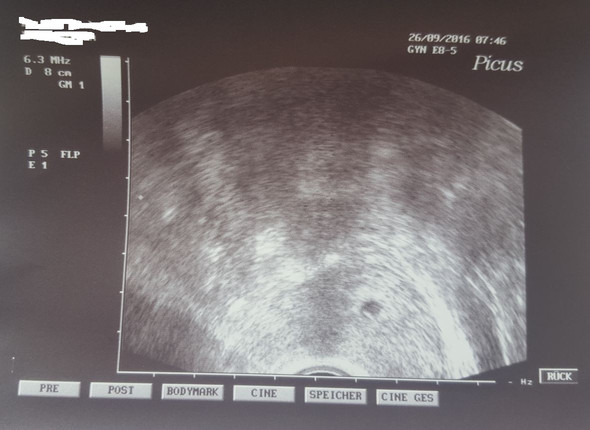

SSW dar, sondern erscheint leicht queroval Hier wurde zwar nicht gemessen, aber in Relation zur Gebärmuttergröße kann man den Durchmesser der Fruchthöhle auf ca einen Zentimeter schätzen Auch hier ist der Embryo noch nicht erkennbar Ultraschallbild 53 SSW Ein weiteres Ultraschallbild vom 3 der 6 Schwangerschaftswoche (53). 6 4 ssw ultraschall nur fruchthöhle Anzeichen, Symptome & Ultraschall in der 6 SSW In der 6 Schwangerschaftswoche kann im Ultraschall der Herzschlag des Babys bereits sichtbar werden, auf jeden Fall ist die Fruchthöhle als schwarzes Oval und der bohnenförmige Embryo erkennbar 6Schwangerschaftswoche (6. Ultraschall in der 61 SSW nur Fruchthöhle und Dottersack sichtbar Tamara92 1 0812 Uhr in Schwangerschaft Hallo zusammen Ich bin 28 Jahre und bin nach einer 2 jährigen Kinderwunschbehandlung während der ersten ICSI schwanger geworden🥰.

Vielleicht ist es noch zu früh und du bist noch gar nicht in der 6 Woche. Auf dem Ultraschall hat der FA dann aber bisher nur eine leere Fruchthöhle gesehen und die Schwangerschaft aufgrund der Größe der Fruchthöhle auf 5W3T errechnet Er sagte, für diesen Zeitraum sei die Entwicklung normal, manchmal sehe man schon einen Dottersack, dieser bilde sich aber oftmals Ende der 6 Woche. Re Keine Fruchthöhle 6ssw Hallo, der Anstieg des HCG bedeutet, dass eine SS vorliegt und ein Trophoblast vorhanden ist(der produziert das HCG) Bei SSW 5 ist nur der Dottersack beim US darstellbar.

Auf dem Ultraschall hat der FA dann aber bisher nur eine leere Fruchthöhle gesehen und die Schwangerschaft aufgrund der Größe der Fruchthöhle auf 5W3T errechnet Er sagte, für diesen Zeitraum sei die Entwicklung normal, manchmal sehe man schon einen Dottersack, dieser bilde sich aber oftmals Ende der 6 Woche. 6 ssw kein embryo nur fruchthöhle und dottersack Fruchthöhle mit Dottersack, aber kein Embryo Auf dem durchgeführten Ultraschall zeigte sich erneut die Fruchthöhle, mit Dottersack, aber war von der Größe her nur einen Millimeter (auf 8,8mm) angewachsen, was der 5W5T entsprechen würde. Ultraschall gebraucht Ultraschall kein Herzschlag 64 SSW Frage von Bia74, 6 SSW Hallo, bin neu hier und auch im Moment völlig aufgelöst Vor zwei Wochen wurde die SS festgestellt und nur die Fruchthöhle war zu sehen Gestern war ich nun wieder zum US und bin in der 64 SSW.